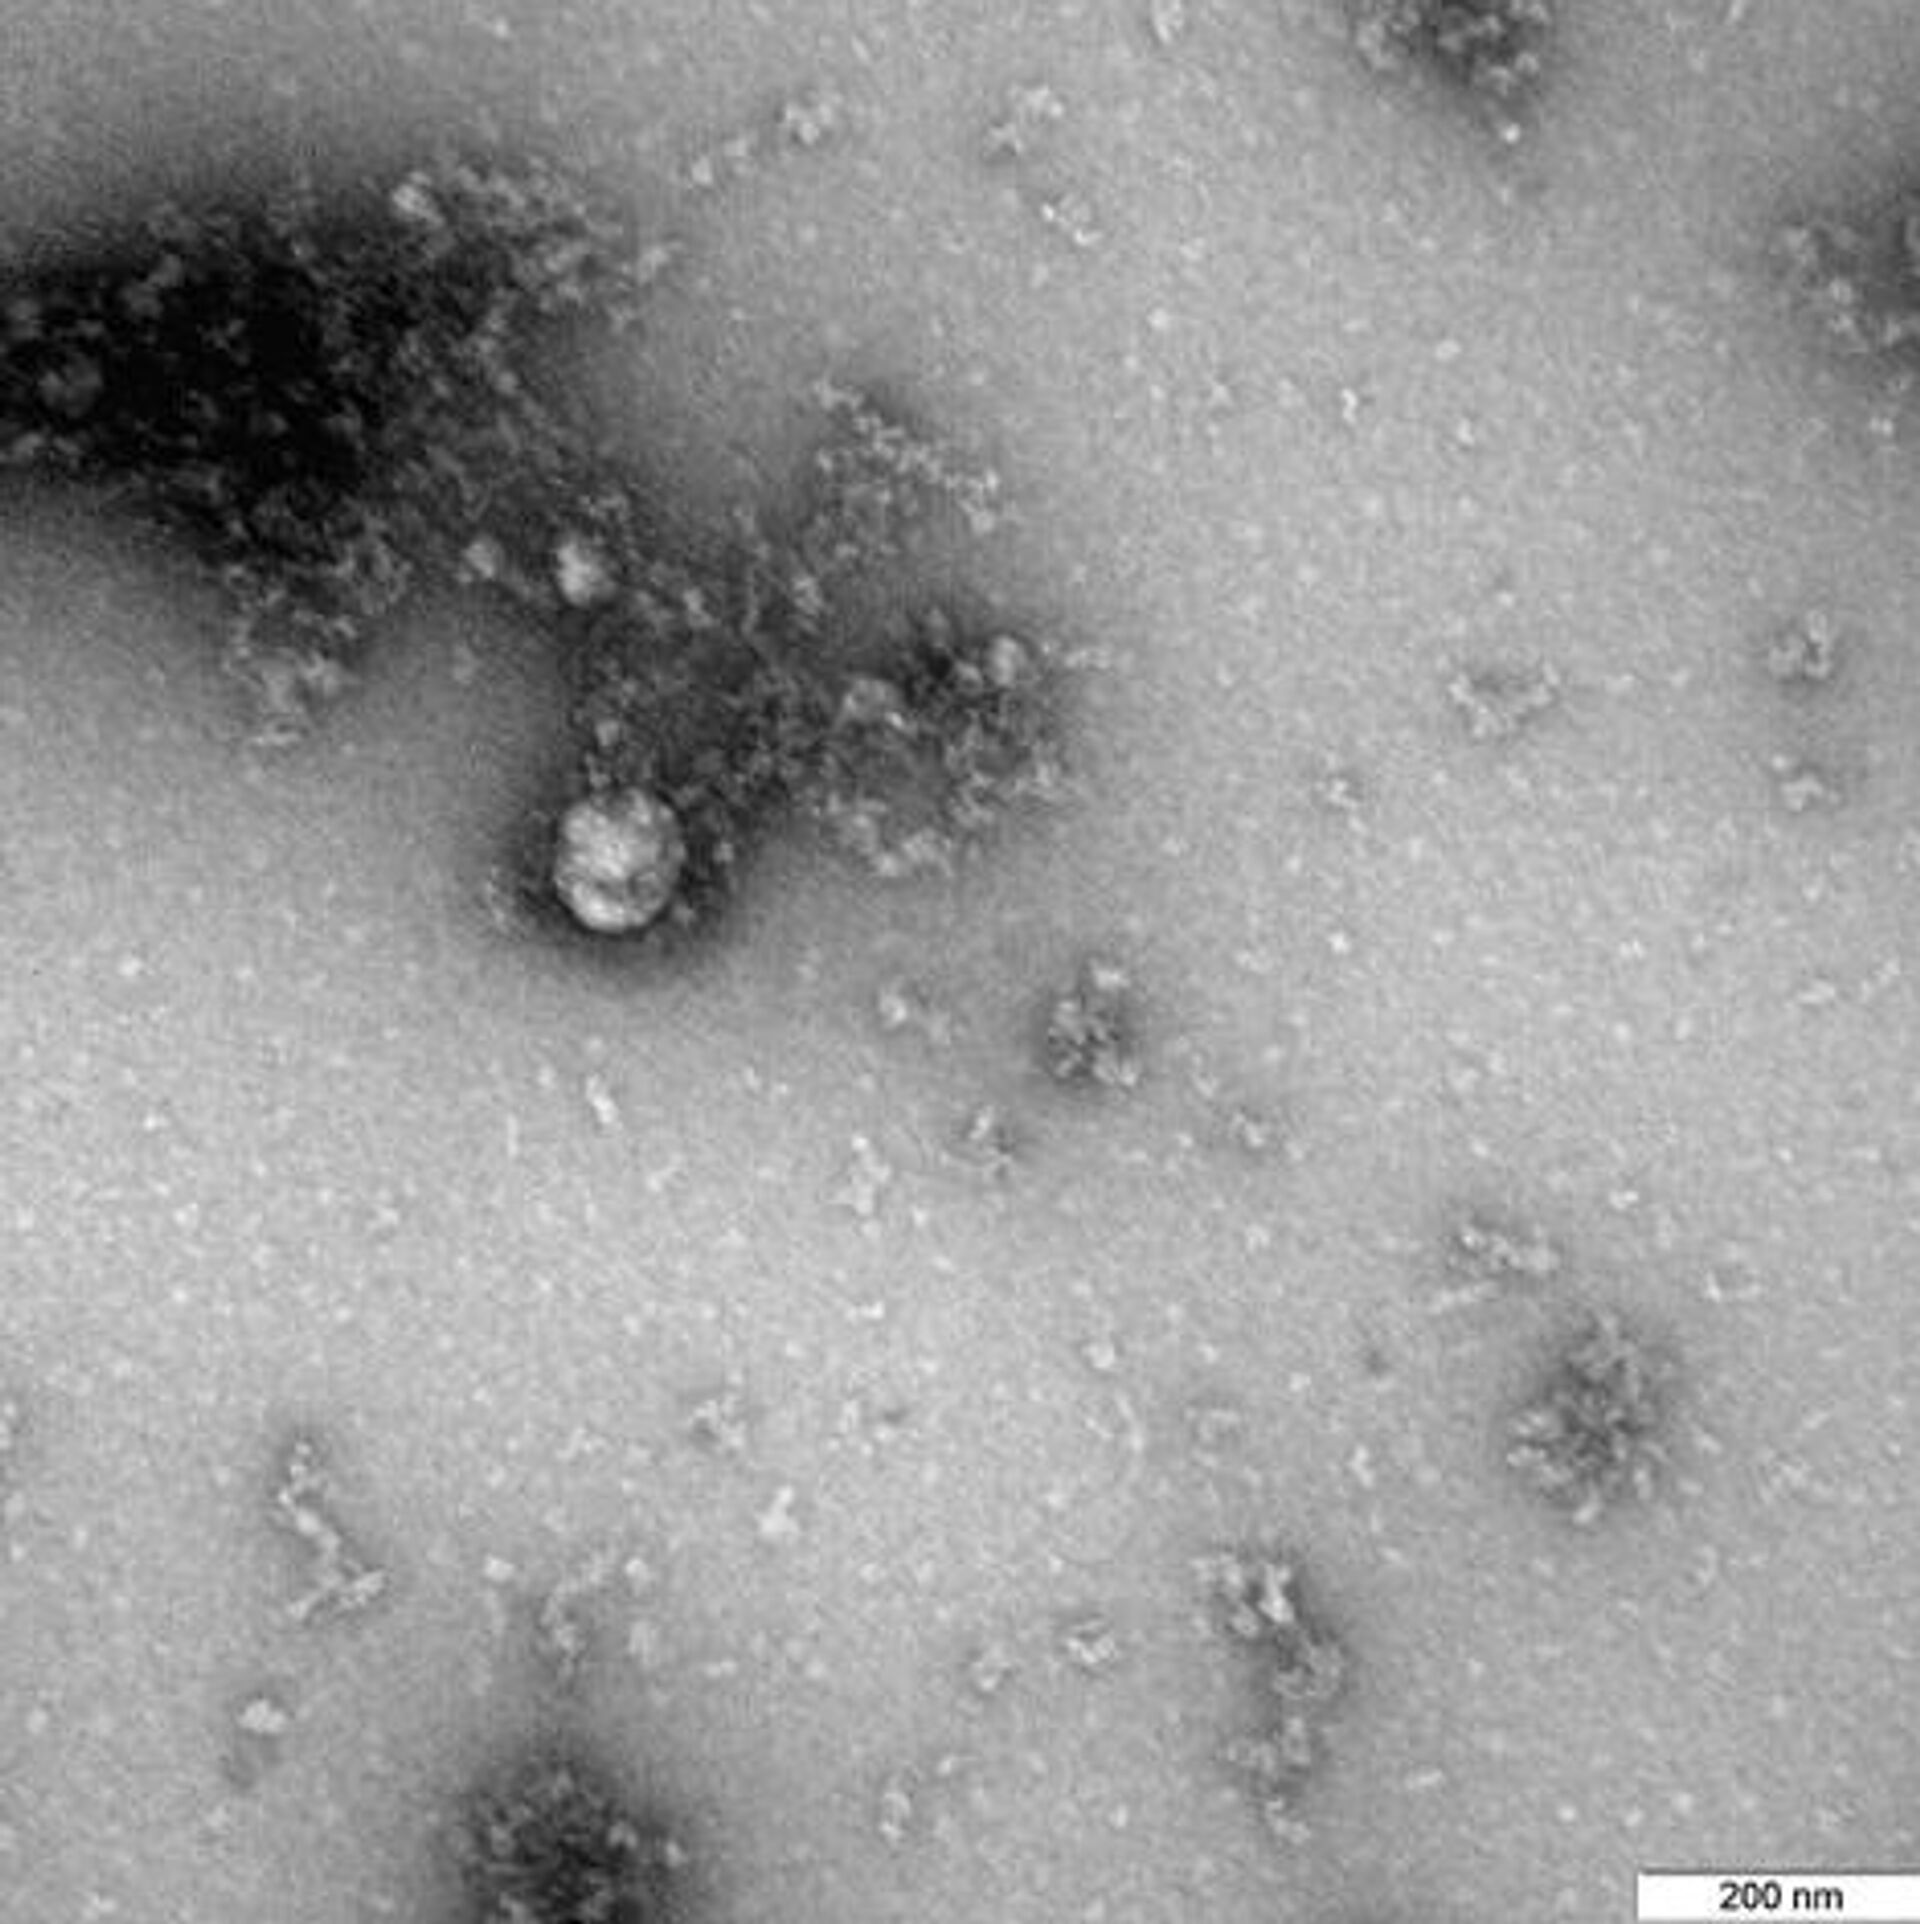

Для "британского" штамма COVID-19 выделили специфичные симптомы

© Фото : РоспотребнадзорФотография под микроскопом британского штамма коронавируса

Фотография под микроскопом британского штамма коронавируса - РИА Новости, 1920, 27.01.2021

МОСКВА, 27 января/ Радио Sputnik. Кашель, боль в горле, усталость, мышечные боли и лихорадка больше распространены у тех, кто заразился "британским" штаммом COVID-19, сообщает Sky News со ссылкой на Управление национальной статистики Великобритании (ONS). Но при этом такие пациенты реже жалуются на отсутствие запахов и вкусов.

Проведенное в этой связи исследование не выявило различий в интенсивности таких симптомов, как одышка и головные боли, говорится в статье.